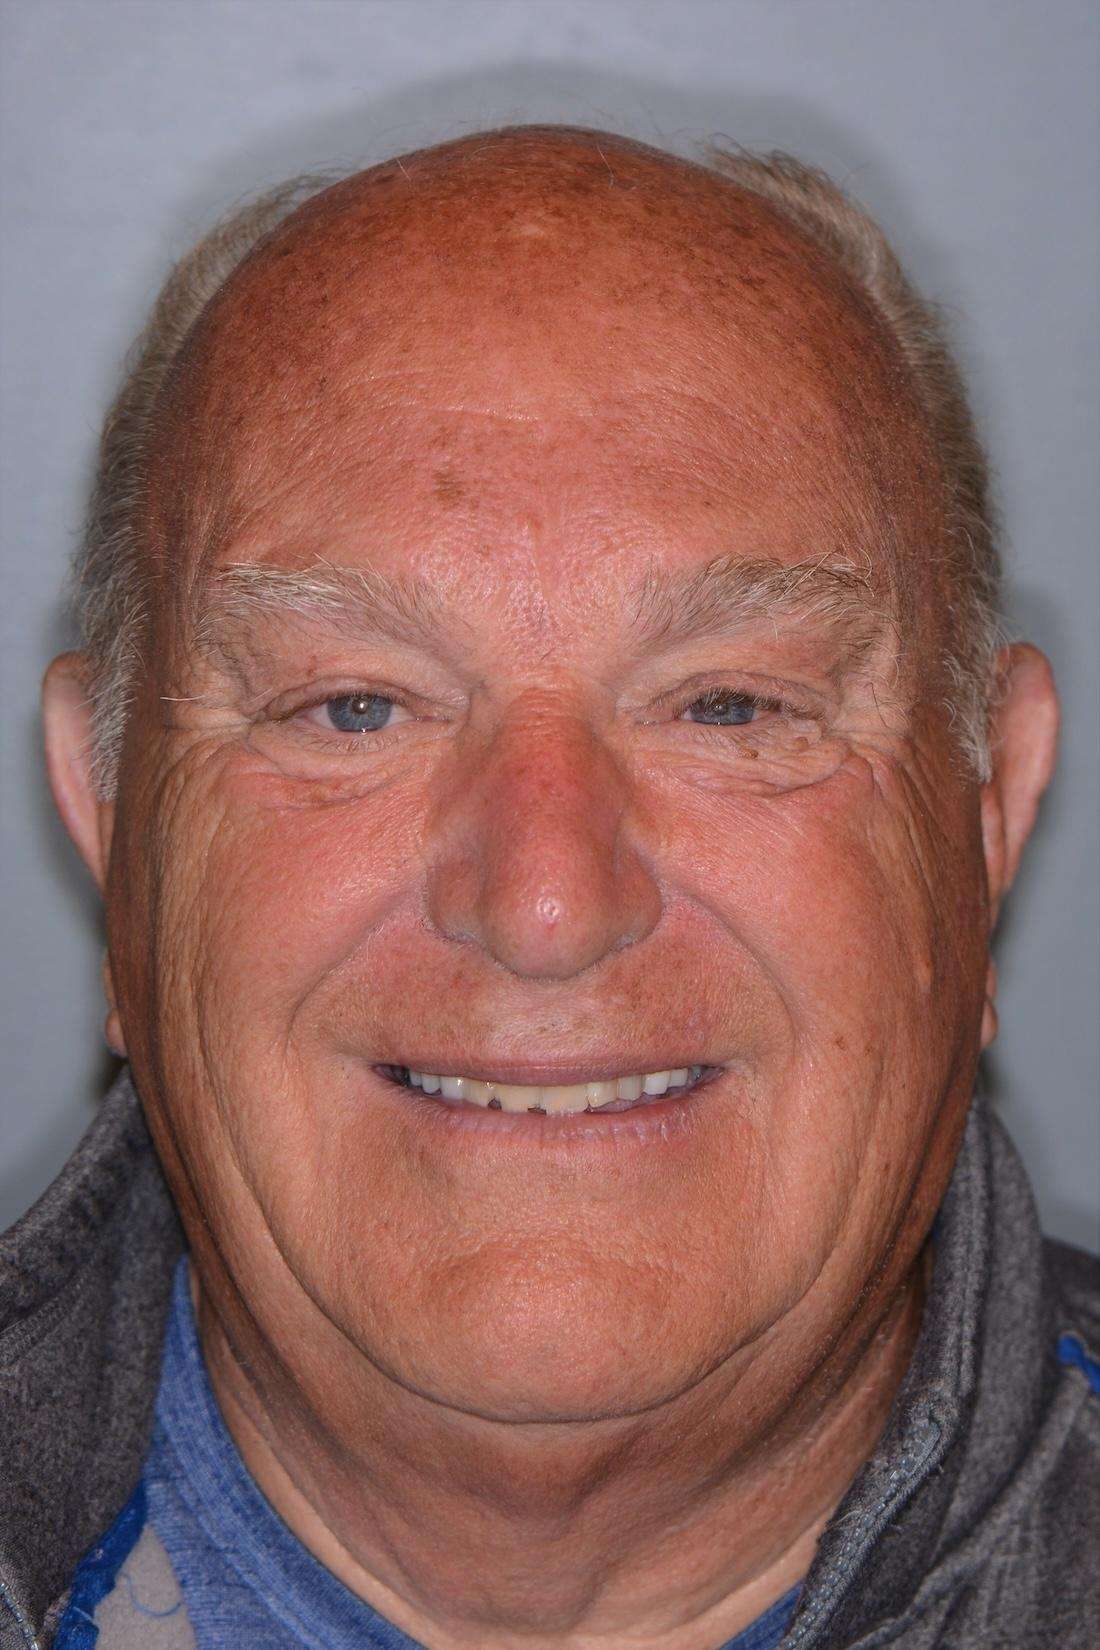

I placed five porcelain crowns on the upper front teeth, carefully matching the color, shape, and translucency to the patient’s existing crowns. Through the use of digital photography and excellent communication with the dental lab, we were able to achieve a seamless, natural look. The new crowns not only restored function but also created a whiter, brighter, and more confident smile.

This case is a wonderful example of how porcelain crowns can completely rejuvenate a smile, while still blending beautifully with existing restorations. I especially enjoyed the artistry involved in achieving such a natural-looking result, and the patient was thrilled with their transformation.